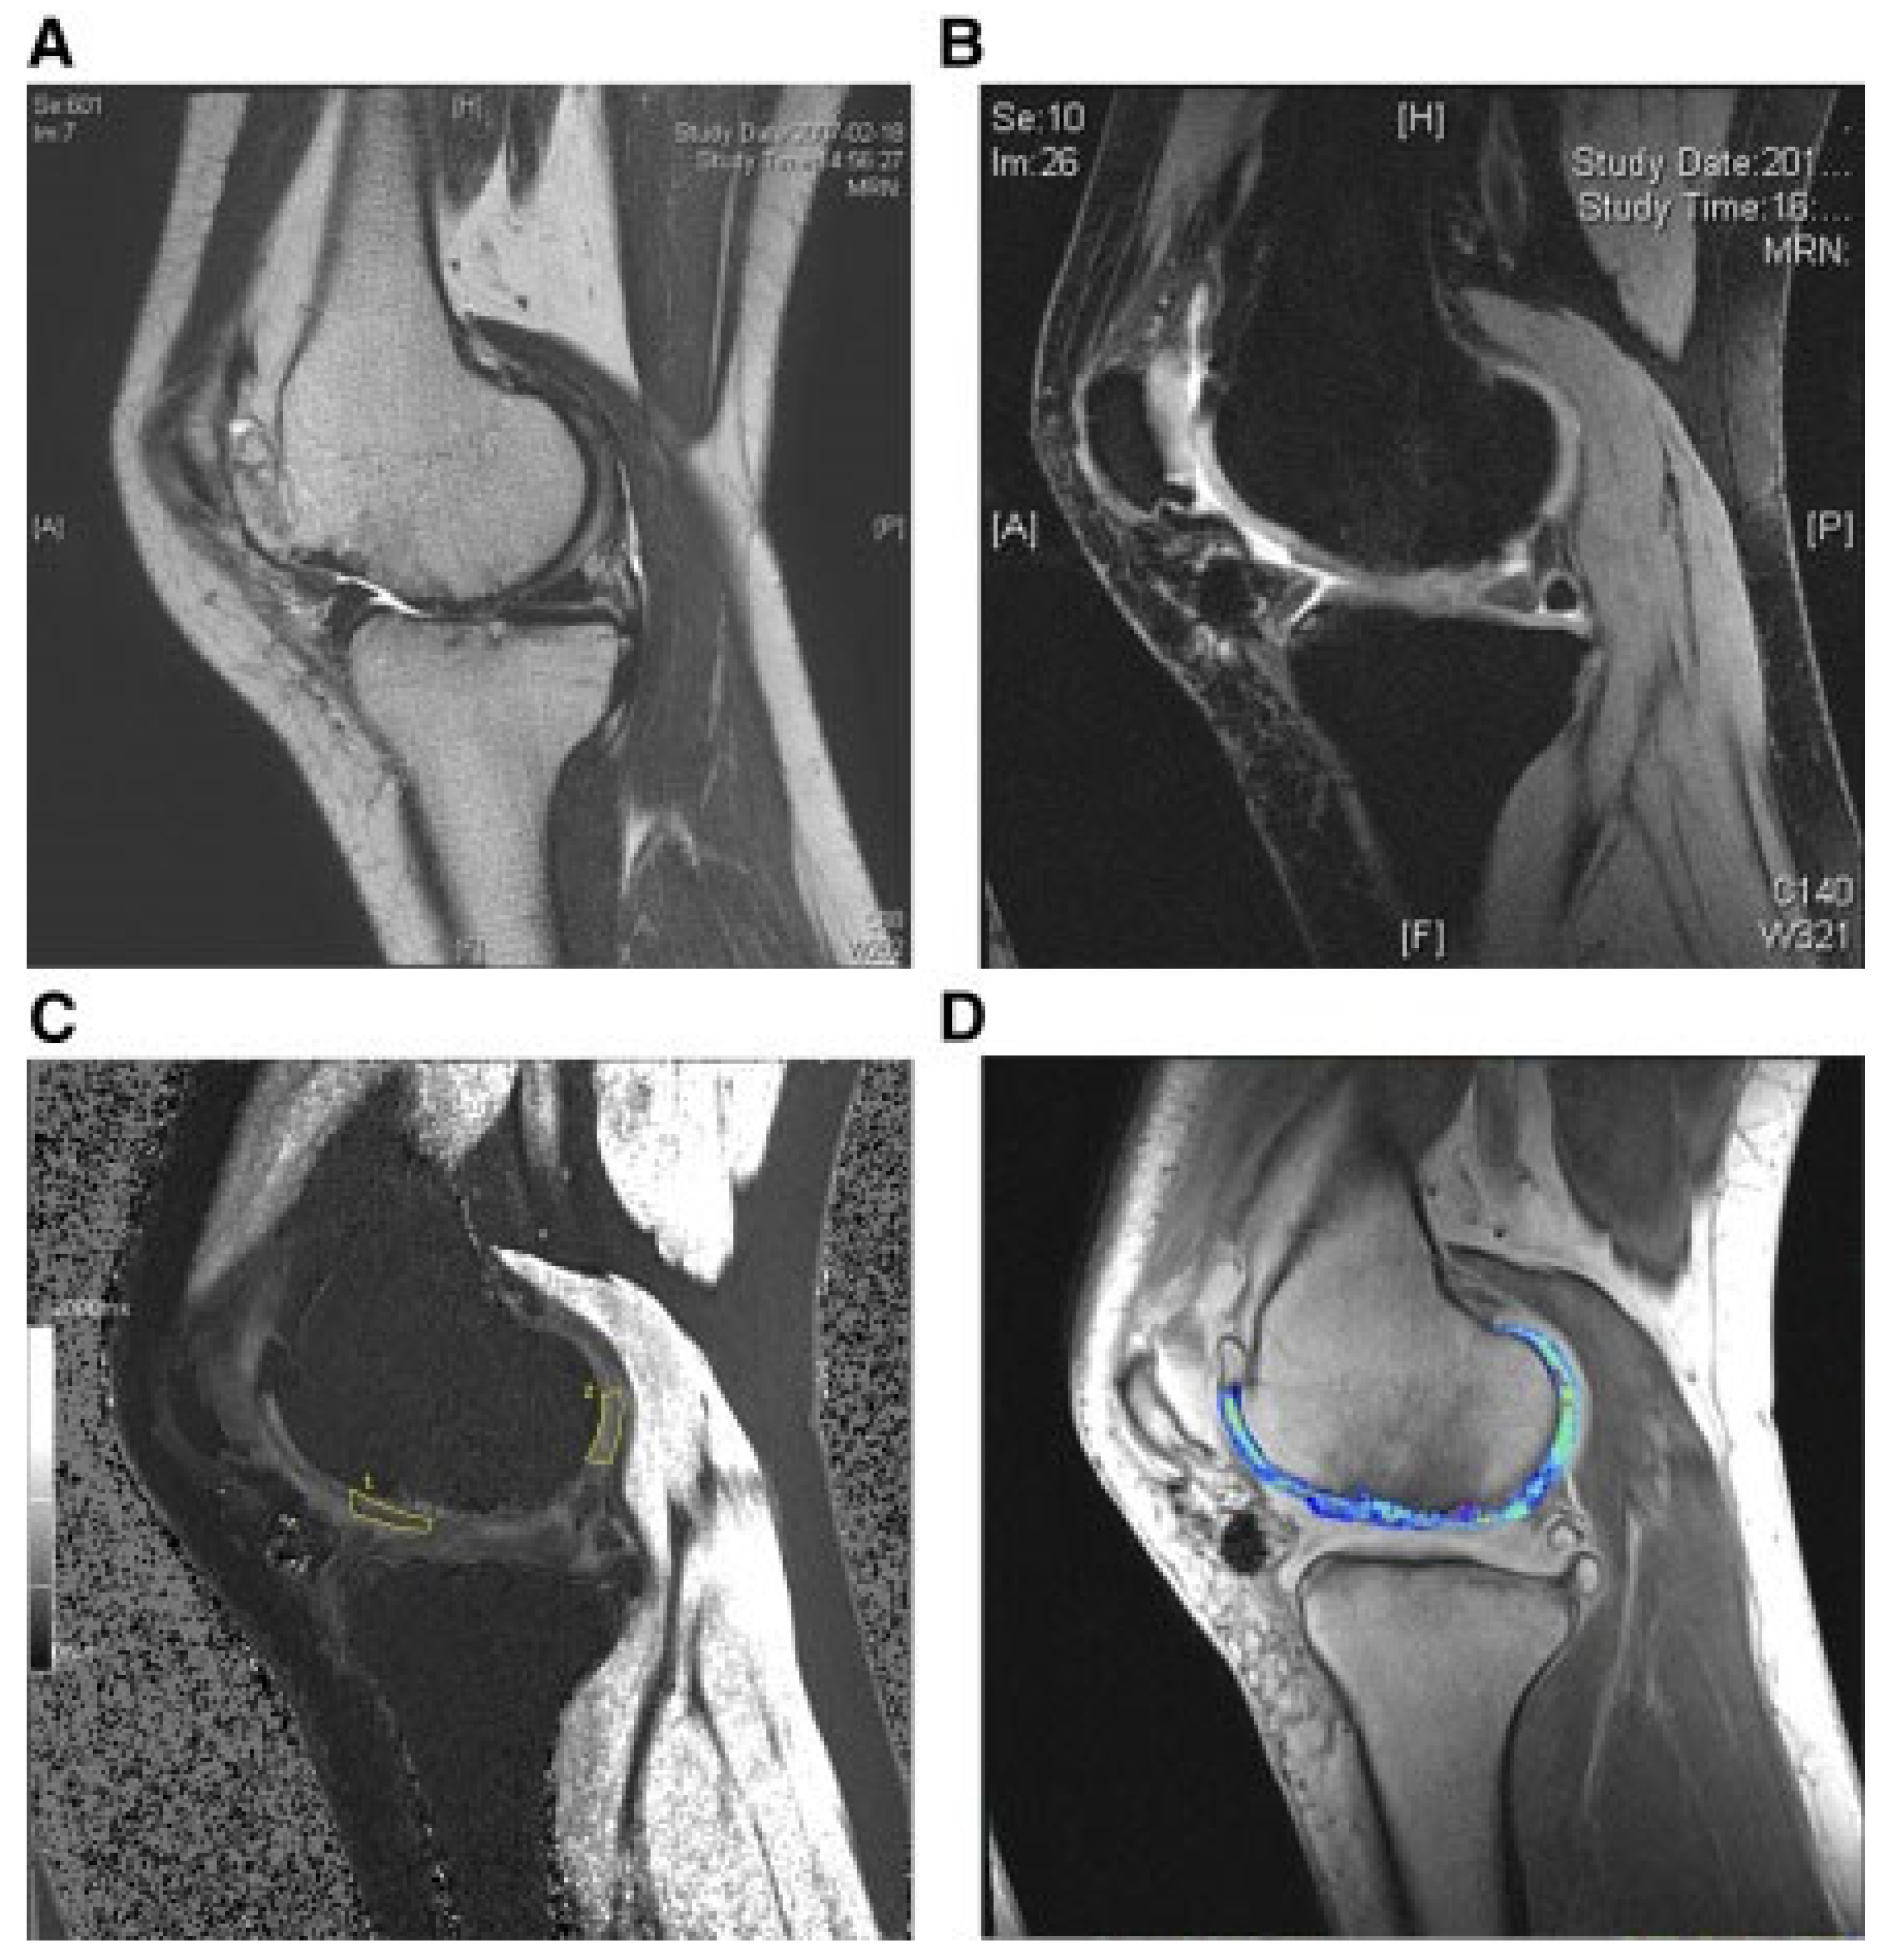

| Park et al. [118] | 2017 | K–L grade III knee osteoarthritis and ICRS grade IV lesions | N = 7; Females = 5; Males = 2; Mean age = 58.7 years | Allogeneic HUCB-MSCs | Surgical implantation of a complex containing stem cells and hyaluronic acid hydrogel (0.5 × 107) | 7 years | Maturing repair tissue was observed at the 12-week arthroscopic examination. The 100 mm VAS and IKDC scores changed from 49.1 and 39.1 to 19.3 and 63.2, respectively, at 24 weeks. |